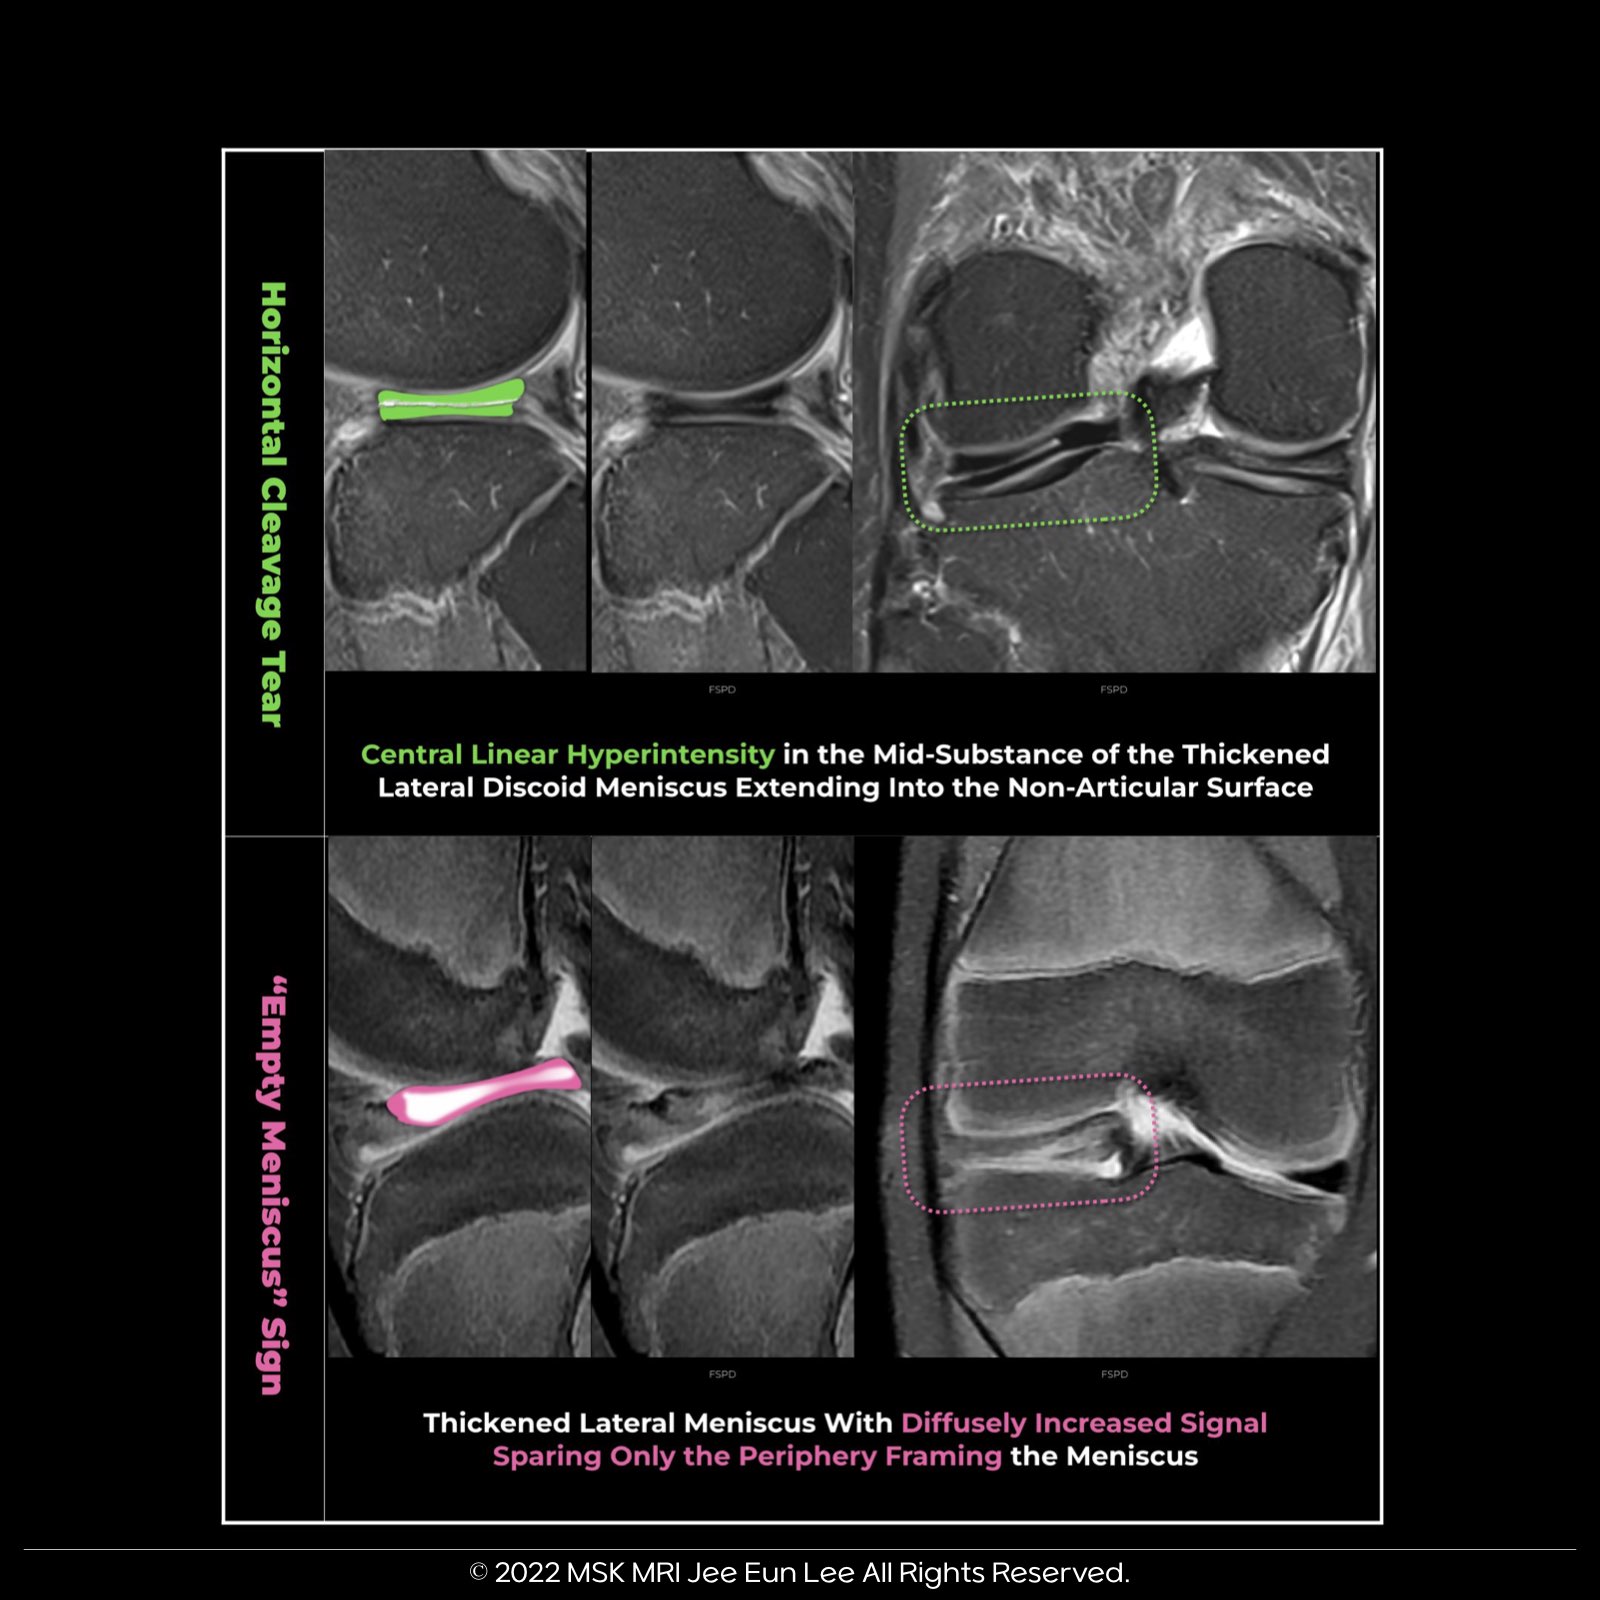

- Criteria: Increased signal and shape deformation may indicate a tear. Horizontal cleavage tears are particularly suspicious in children under 10.

3️⃣ Notable Signs:

- Mucinous Degeneration: Thick grade 2 signal on sagittal images.

- Empty Meniscus Sign: Diffuse signal with hypointense borders, associated with chronic symptoms.